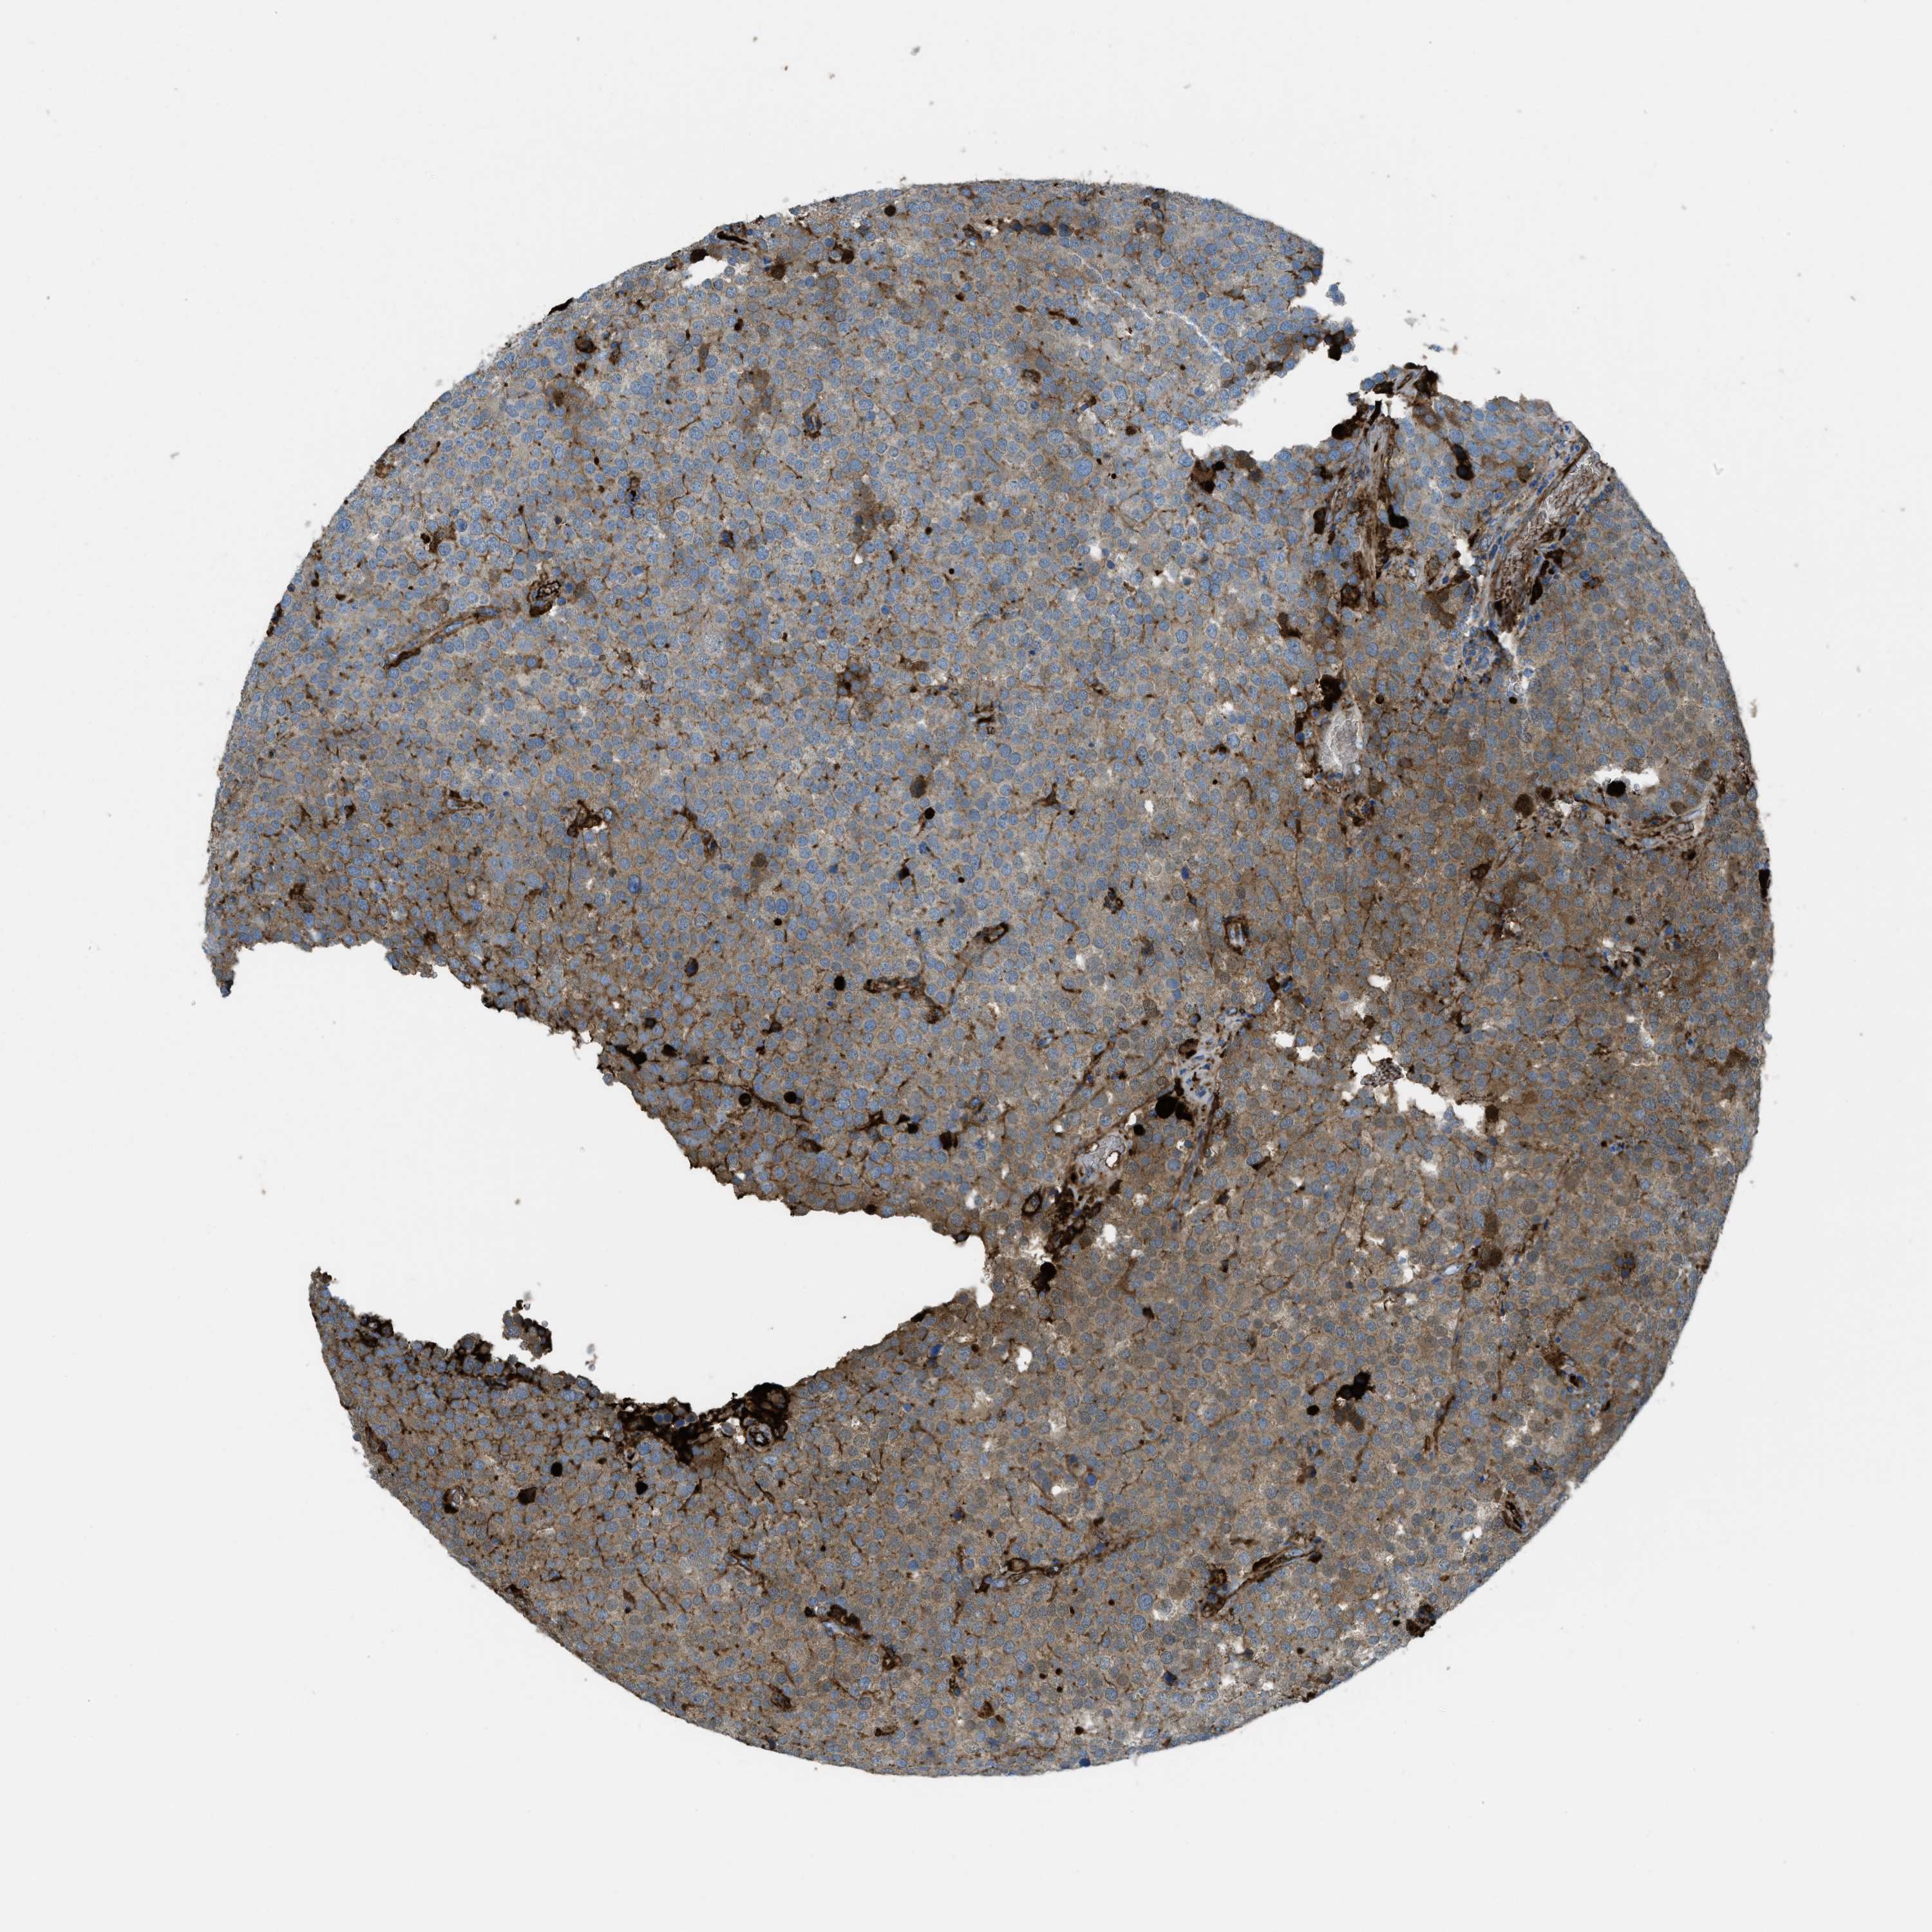

TESTIS CANCER - Protein expressioni

A mouse-over function shows sample information and annotation data. Click on an image to view it in a full screen mode. Samples can be filtered based on level of antibody staining by selecting one or several of the following categories: high, medium, low and not detected. The assay and annotation is described here.

Note that samples used for immunohistochemistry by the Human Protein Atlas do not correspond to samples in the TCGA dataset.

Antibody stainingi

Antibody staining in the annotated cell types in the current human tissue is reported as not detected, low, medium, or high, based on conventional immunohistochemistry profiling in selected tissues. This score is based on the combination of the staining intensity and fraction of stained cells.

Each image is clickable and will lead to virtual microscopy that enables deeper exploration of all samples and also displays staining intensity scores, fraction scores and subcellular localization as well as patient and tissue information for each sample.

Antibody HPA017750

Staining

High

Medium

Low

Not detected

Intensity

Strong

Moderate

Weak

Negative

Quantity

>75%

75%-25%

<25%

None

Location

Nuclear

Cytoplasmic/membranous

Cytoplasmic/membranous,nuclear

Carcinoma, Embryonal, NOS

Seminoma, NOS